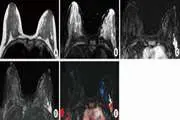

Semiquantitative dynamic contrast enhanced MRI for accurate classification of complex adnexal masses

To identify the best dynamic contrast-enhanced (DCE) magnetic resonance imaging (MRI) descriptive parameters in predicting malignancy of complex ovarian masses, and develop an optimal decision tree for accurate classification of benign and malignant complex ovarian masses